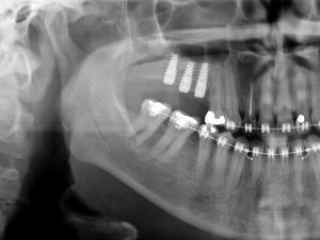

Enxerto de seio maxilar